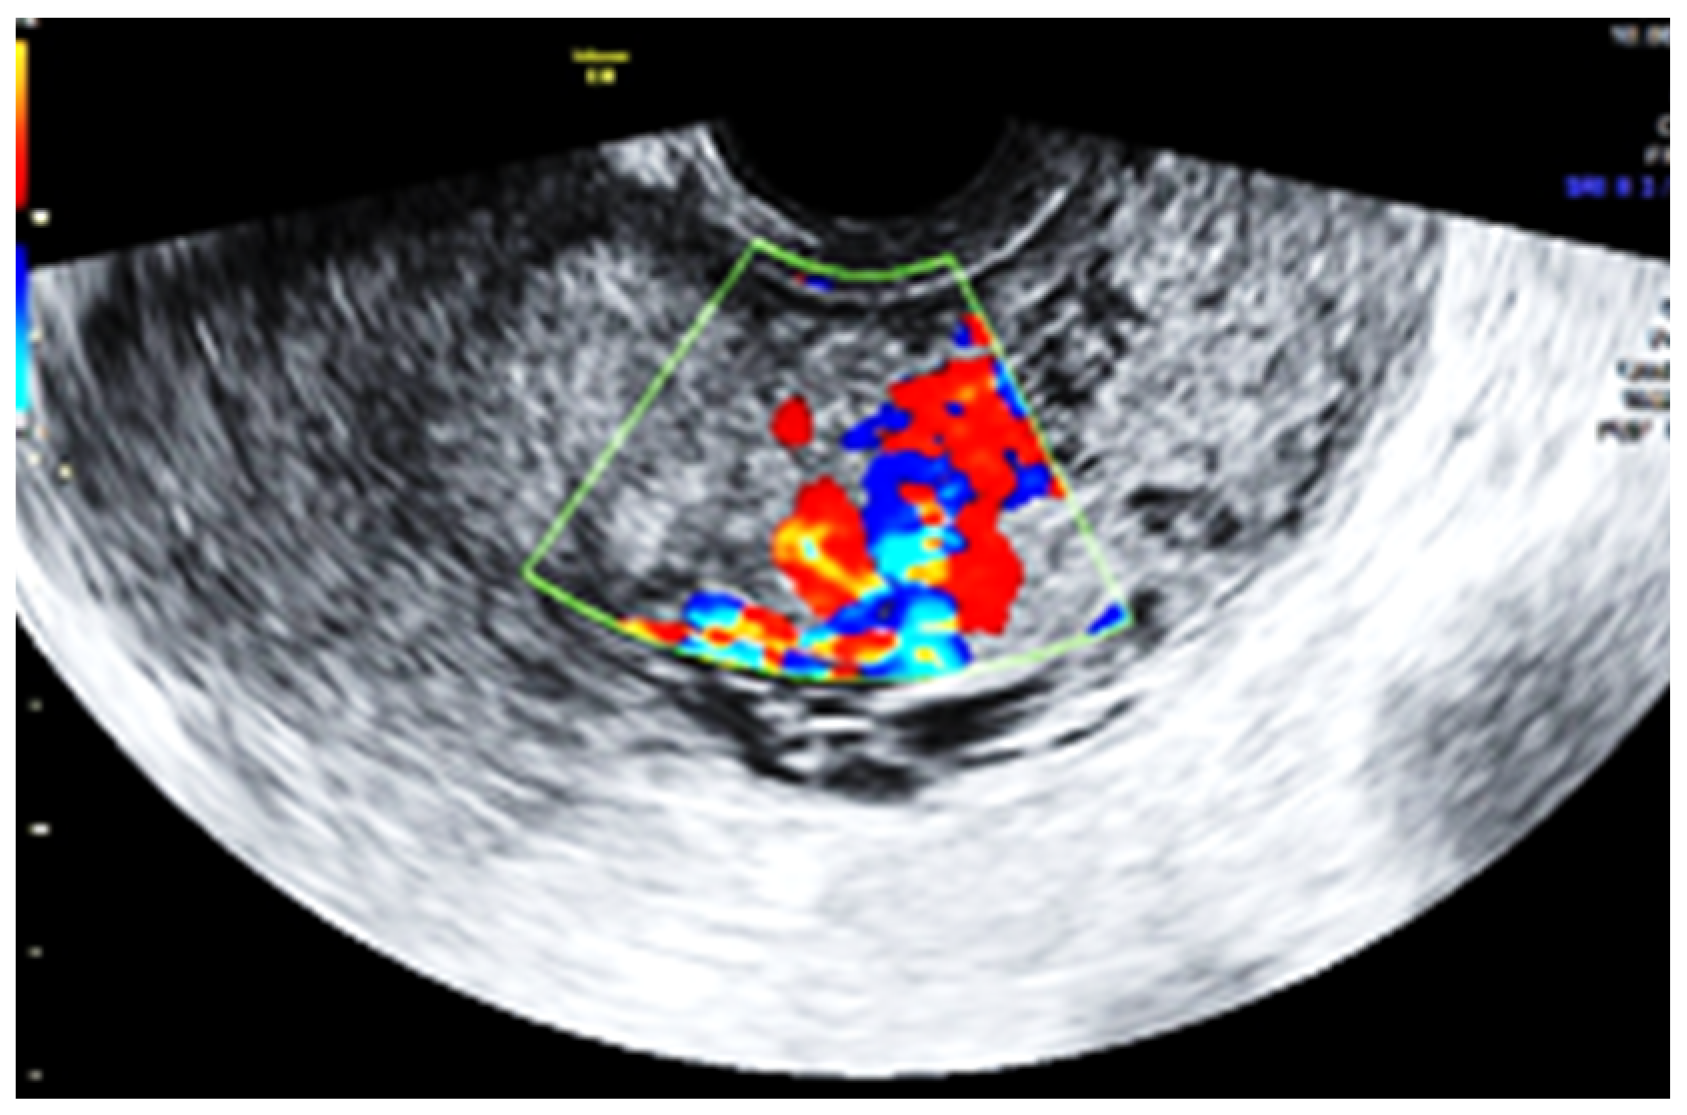

Subsequent ultrasound examination revealed a uterus with a homogeneous structure measuring 67/52/61 mm (Figure 1). However, in the lower portion of the uterine cavity and the upper part of the cervical canal, there was a non-homogeneous hyperechogenic mass measuring 72/30/75 mm (Figure 2). The mass exhibited numerous vessels (Figure 3), while the lower portion of the cervix appeared normal with a length of approximately 13 mm (Figure 4).

Figure 3.

The mass with increased vascularity.

Based on the ultrasound findings, we suspected a diagnosis of choriocarcinoma originating from the placental site. The patient had a low beta-HCG level (15.5 IU), and an MRI confirmed that the uterine mass consisted solely of placental tissue, without the involvement of the uterine walls or adjacent organs.

Several comparisons can be drawn between the microenvironment of the placenta accreta spectrum and tumor behavior. Both conditions require the ability of cells to evade the local immune system, induce angiogenesis, and promote invasion []. This may explain the proliferation of placental tissue even though the uterine cavity appeared normal after placental removal during the cesarean section. Extensive neovascularization is a prominent feature in most PAS cases, as observed in the increased vascularity of the intrauterine mass detected during our patient’s ultrasound examination. Comparative analysis of syncytiotrophoblastic cells from PAS cases and normal placenta specimens has suggested a proangiogenic phenotype in PAS [].